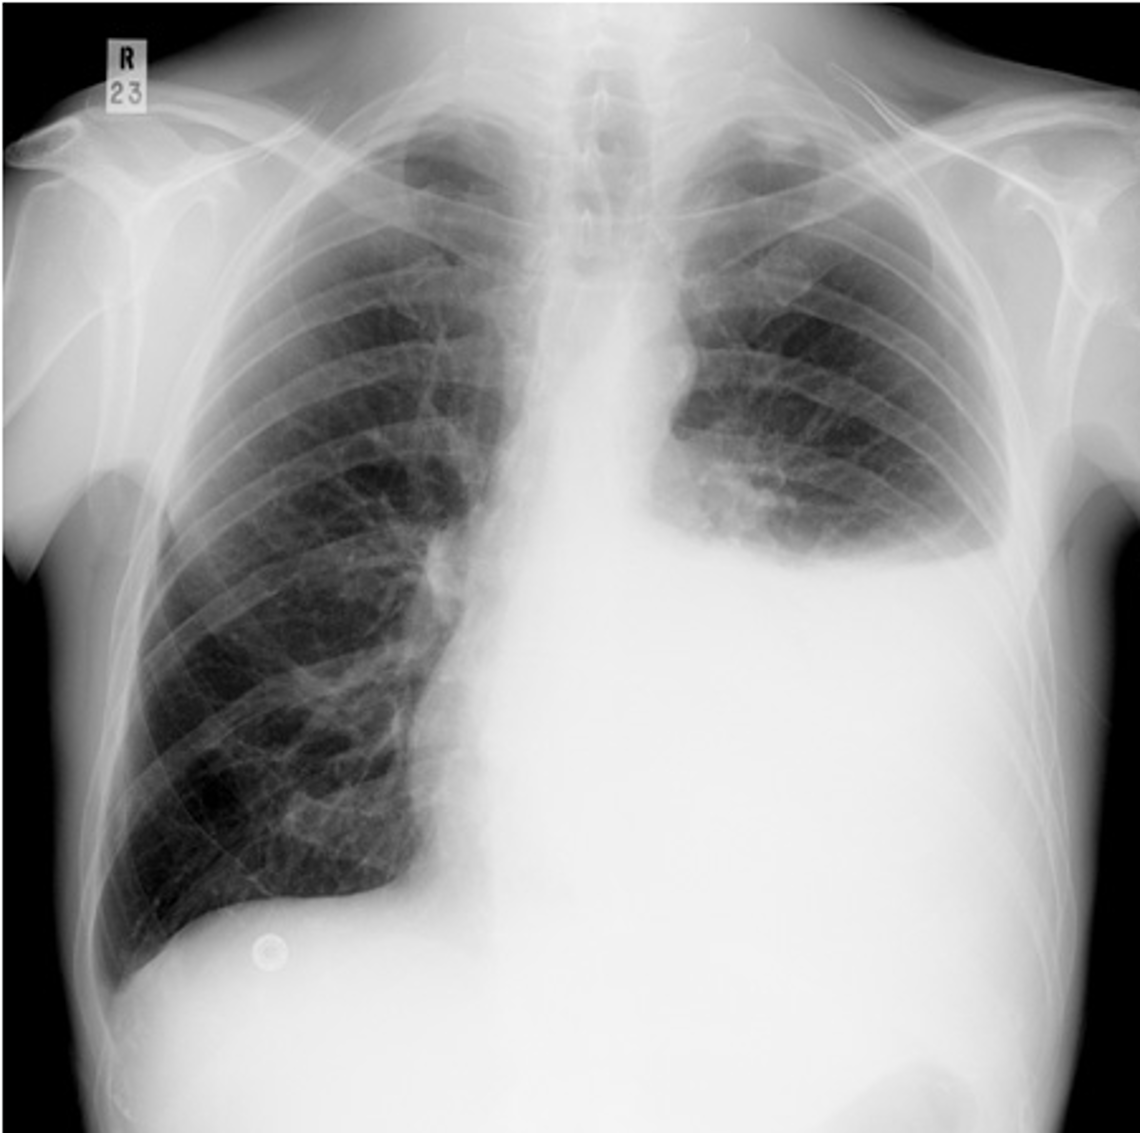

Pleural effusion with tracheal deviation